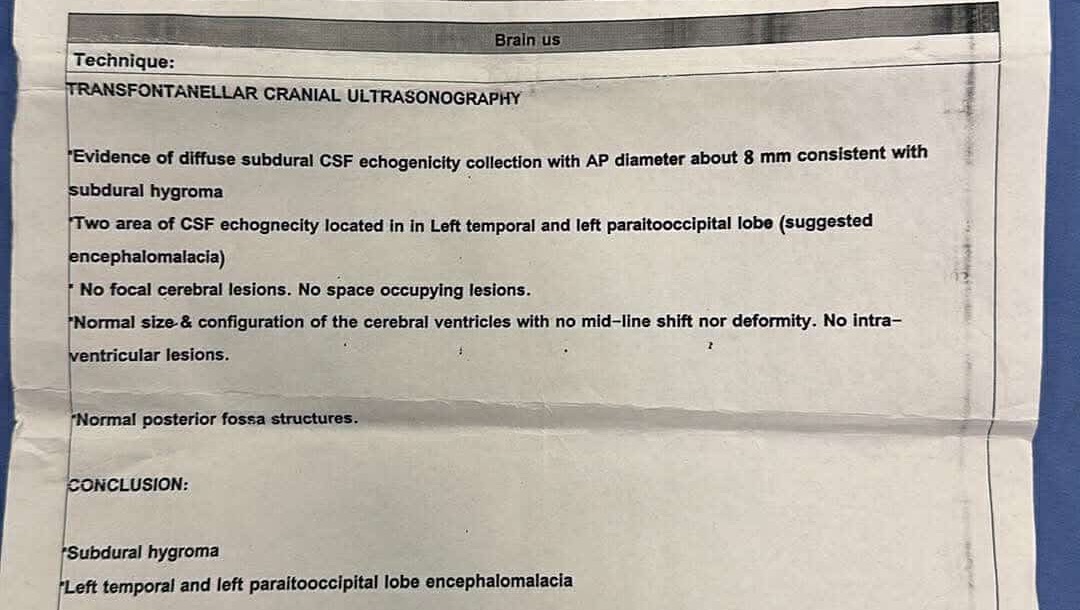

A 3-month-old baby in my family is facing a life-threatening brain condition. Medical reports and imaging confirm serious neurological injury that requires immediate, specialized treatment outside Gaza—care that is not available here.

Without urgent medical intervention, this baby is at high risk of:

• Permanent brain damage

• Severe developmental delays

• Seizures and lifelong disability

• Or loss of life

Doctors have outlined an initial urgent treatment plan.

The first stage requires three specialized medical injections to stimulate body and height growth as part of stabilizing his overall development.

The cost of each injection is $1,000,

bringing the total for this first stage alone to $3,000.

This is only the beginning of a much longer medical journey, but these injections are critical and cannot be delayed.